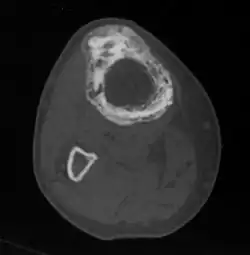

Die übermäßige Ausscheidung von Calcium kann zu Nierensteinen führen, die vermehrte Knochendurchblutung begünstigt eine Herzinsuffizienz. Durch die übermäßige Teilungsaktivität der Knochenzellen kommt es in etwa 1 % der Fälle zur Entwicklung eines bösartigen Knochentumors. Wenn derartige Komplikationen vermutet werden, ist eine Computertomografie oder Kernspintomografie sinnvoll.

Bildgebende Verfahren

Wesentlich für die Diagnose ist das Röntgenbild, in dem schon im Frühstadium der Erkrankung die Osteolyse nachgewiesen werden kann. Der erhöhte Knochenumbau kann mittels Knochenszintigraphie nachgewiesen werden.